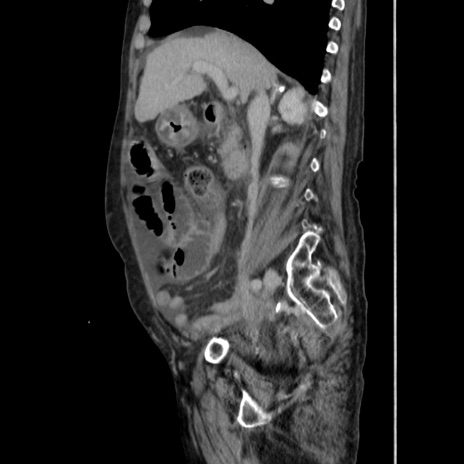

症例31(矢状断像)

【症例】80歳代 女性

【主訴】腹部膨満感

【現病歴】他院にて肝硬変にてフォロー中。1週間前から便秘、腹部膨満感、臍部腫瘤あり受診となる。

【既往歴】肝硬変

【身体所見】腹部膨隆あり、皮膚変化なし、疼痛なし。

【データ】WBC 4600、CRP 0.25